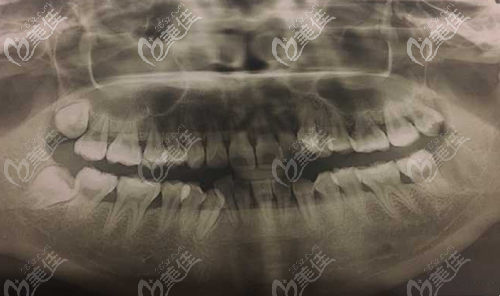

當(dāng)正畸醫(yī)生宣布你需要拔掉多顆正畸牙后,才能做矯正,此時(shí),是不是好擔(dān)心拔牙矯正會(huì)不會(huì)出現(xiàn)什么后遺癥?來(lái)看看真相是怎樣的....... b1607 G0 V0